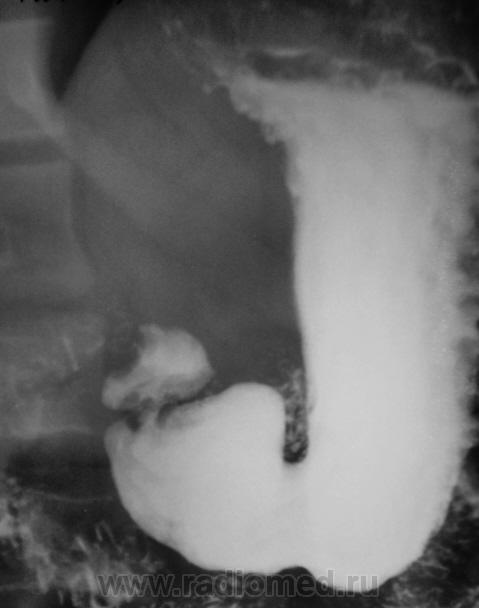

Вообще довольно часто встречающаяся ситуация с военкоматом, когда эндоскосписты, что-то нашли, а "рентген" не нашел. Но в данном случае наоборот - эндоскописты кроме "гастритика" ничего не нашли, рентгенологи дали заключение о наличии язвенной болезни 12-ти перстной кишки. Что делать терапевту, который будет писать акт, что делать эксперту, который будет выносить решение?

Принесли вот такие сгимки, спрашивают мнение.

"Язва" луковицы есть.....и на "рельефе" и на "конутре" "ниша" просматривается. Может у кого то будет другое мнение. послушаем.

На всей серии снимков формально - ниша в луковице. Однако на всех же снимках она хорошо заполнена, нет раздражения - главного косвенного признака... Возможно это в гипотонии? А в заключение - рубцовая деформация...

Релаксация не проводилась.